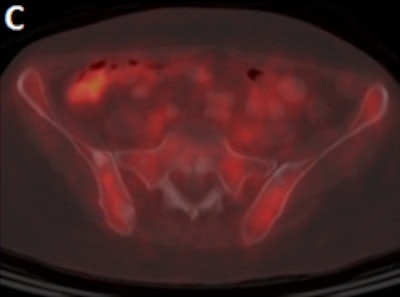

Meanwhile, among women with stage III invasive ductal cancer, 20 (22%) of 89 were upstaged to stage IV from FDG-PET/CT results. All 20 subjects had FDG-avid metastases.

Ulaner cited two reasons for the difference in FDG performance between ductal and lobular cancers. One factor is that FDG is more avid in ductal cancers than lobular ones. The second reason is based on where metastases tend to spread.

"With ductal breast cancer, distant metastases will be in the bone, liver, and lung, which are more easily seen on FDG-PET," he said. "Lobular breast cancer will more often give metastases to the gastrointestinal tract and the peritoneum, which are more difficult to analyze on FDG-PET and may be better evaluated by CT."